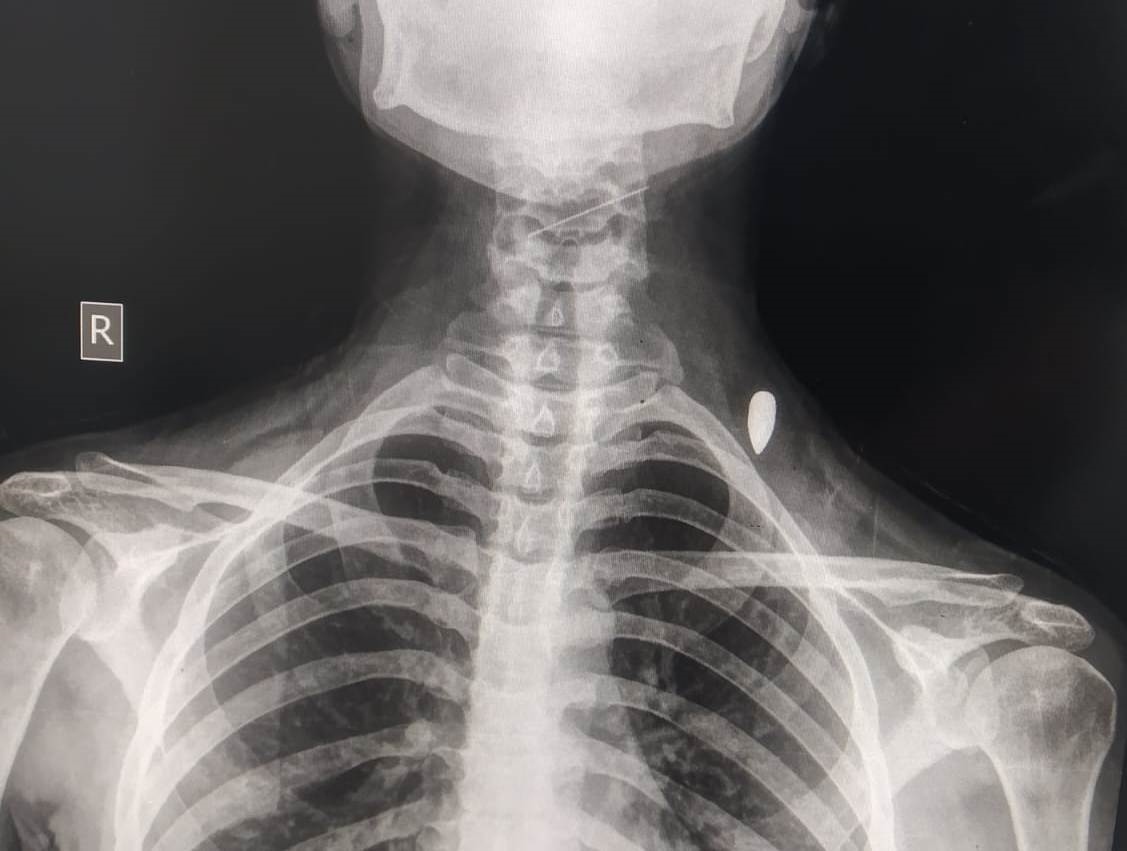

خلال نومها في خيمتها مع عائلتها النازحة قرب شاطئ البحر بمدينة خان يونس جنوب القطاع، استيقظت الشابة الفلسطينية سهير صقر (27 عاماً) مفزوعة، وهي تتألم بشكل كبير جراء اختراق رصاصة إسرائيلية لرقبتها واستقرارها في كتفها الأيسر.

وذكرت صقر أنها توجهت فوراً إلى مستشفى جمعية الصليب الأحمر القريب لتلقي العلاج، لكن الأطباء الذين قرروا إخضاعها لعملية جراحية على الفور، وأكثر من مرة، أوضحوا لها أن "إزالة الرصاصة تمثل خطراً على حياتها لأنها كبيرة وقريبة جداً من الأعصاب، ومن المرجح أن تسبب إزالتها في الوقت الحالي مشكلة في الأعصاب، وقد يؤدي ذلك إلى شلل، ونصحوني بالتعايش مع الرصاصة".

وأضافت في حديثها لـ"عربي21": "الرصاصة تتسبب لي بألم شديد مستمر، وأحياناً لا أستطيع تحريك يدي، ويحدث انتفاخ كبير في منطقة الإصابة، مما يضغط على الأعصاب، وأشعر حينها بوجع وثقل في رأسي ودوران، ولا أستطيع فعل أي شيء سوى أخذ مسكن للألم".

خلال نومها في خيمتها مع عائلتها النازحة قرب شاطئ البحر بمدينة خان يونس جنوب القطاع، استيقظت الشابة الفلسطينية سهير صقر (27عاما) مفزوعة وهي تتألم بشكل كبير جراء اختراق رصاصة إسرائيلية لرقبتها واستقرت في كتفها الشمال.

وذكرت صقر أنها توجهت فورا إلى مستشفى جمعية الصليب الأحمر القريب لتلقي العلاج، لكن الأطباء الذين قرروا إخضاعها لعملية جراحية على الفور وأكثر من مرة، أوضحوا لها أن "إزالة الرصاصة يمثل خطرا على حياتها لأنها كبيرة وقريبة جدا من الأعصاب، ومن المرجح أن تسبب إزالتها في الوقت الحالي بمشكلة في الأعصاب ويؤدي ذلك إلى شلل ونصحوني بالتعايش مع الرصاصة".

وأضافت في حديثها لـ"عربي21": "الرصاصة تتسبب لي بألم شديد مستمر، وأحيانا لا استطيع تحريك يدي ويحدث انتفاخ كبير في منطقة الإصابة مما يضغط على الأعصاب وأشعر حينها بوجع وثقل في رأسي ودوران، ولا استطيع فعل أي شيء سوى أخذ مسكن للألم".